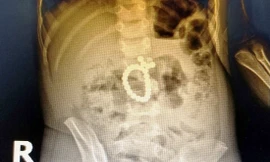

Từ khóa: "nguy hiểm của nam châm chơi trẻ em"

1 kết quả